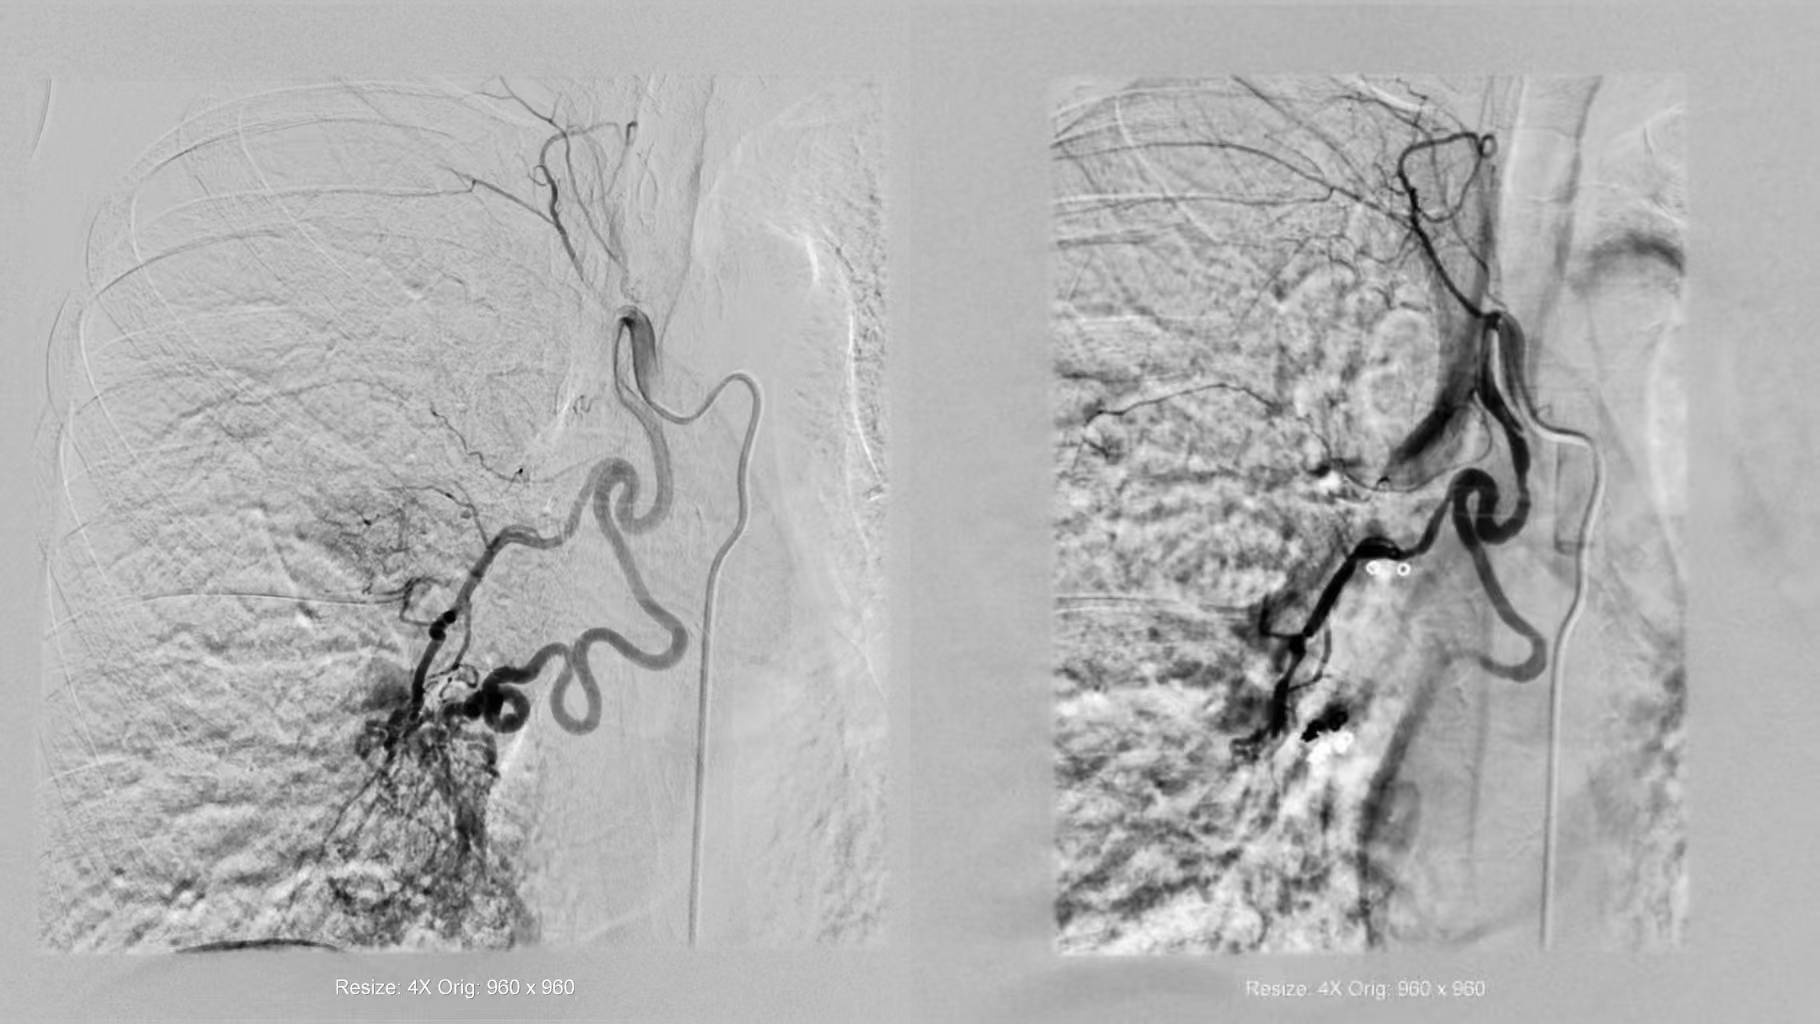

3天前,冯阿姨晨起咳痰见血丝,没成想很快发展成大口咯血。家人将冯阿姨紧急送往西安大兴医院渭水园院区后,术前CTA检查显示其支气管动脉严重迂曲扩张,术中更发现支气管动脉-静脉瘘——这正是咯血的“元凶”。

配准 超选

栓塞+超选 栓塞

术前CTA与术中DSA影像精准配准,3D Fusion技术让迂曲血管立体呈现,Overlay技术将血管走形叠加在实时画面上——原本“盲探”的出血点,瞬间“一眼锁定”。微导管在导航引导下快速且精准到达靶血管,快速注入栓塞剂顺利止血。从麻醉到手术结束,仅用45分钟,较传统手术缩短近2小时。

术前造影 (L) (西安大兴医院) 术后造影(L)

术前造影(R) 术后造影(R)